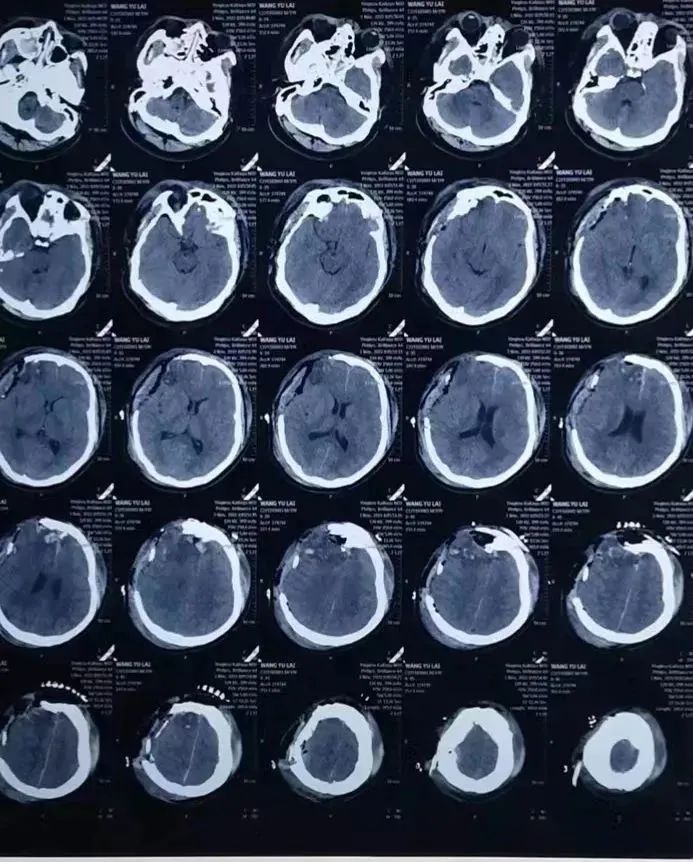

60岁的李大爷,因交通事故伤及头部送到我院就医。入院时病情极其危重,伴有头痛、头晕、恶心,颅脑CT提示为双侧额顶骨、右侧颞骨、左侧枕骨见骨质断裂错位,左侧顶骨轻度向内凹陷。双侧硬膜外出血,脑挫烈伤,蛛网膜下腔出血双侧陈旧腔梗。

一般情况下颅内急性出血在50—70ml左右即可引起脑疝,可李大爷的出血量已经达到了惊人的180ml,必须马上进行抢救。因颅内的上矢状窦是脑内静脉血回流出颅的必经血管,发病急,进展快,短时间内可出现病情严重恶化,手术风险极高,术中患者随时可因颅内大出血危及生命。考虑到种种原因,家属决定放弃手术,采取保守治疗的方式。

(治疗前影像报告)

“该患者颅脑损伤位置下有一重要的解剖血管即上矢状窦,结合影像资料上矢状窦损伤可能性极大,而上矢状窦损伤引起的双侧硬膜外血肿非常罕见,且十分严重,几乎均需要手术干预。通过保守治疗恢复良好的病例则非常少见,如处理不当将会出现大出血危及患者生命。”神经外科主任吕松林介绍道。